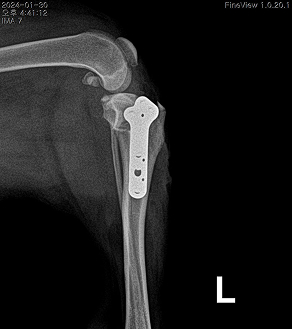

AFTER